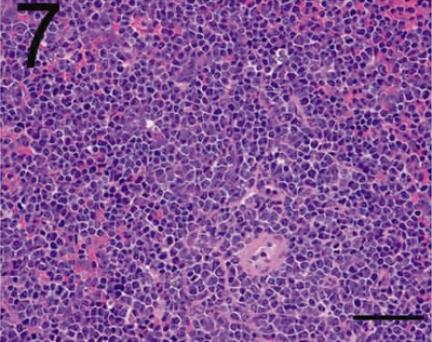

Although spontaneously occurring neoplasms have been reported repeatedly in F344, SD and Wistar rats, which are commonly used strains for routine toxicologic and carcinogenicity studies, there are only a few reports of malignant lymphoma or lymphatic leukemia except for large granular lymphocytic leukemia (LGL) in F344 rats. Malignant lymphoma (lymphosarcoma) is thought to be uncommon in F344 rats. The authors encountered malignant lymphomas of the non-LGL leukemia type with characteristic pathologic features in WBN/Kob rats. The mean age at onset of the disease in all 13 affected rats (8 males and 5 females) was about 60 weeks. Common and characteristic clinical signs were abnormal gait with hind limb paralysis. Macroscopically, the enlargement of the lymph nodes, spleen and liver was slight to moderate. Scattered multiple white-to-gray nodules encompassed the aorta and assumed a bead-like appearance near the thoracic and lumbar vertebrae. Histopathologically, neoplastic proliferative changes were predominant in the bone marrow tissue of the entire body, and many tumor cells infiltrated the spleen and several lymph nodes. The most striking histological features were constant and severe infiltration of tumor cells in the adipose tissue and skeletal muscle adjacent the thoracic and lumber vertebrae. Immunohistochemically, all tumor cells were positive for B-cell markers (PAX-5, CD79a and CD45) and negative for CD3. From the results of immunohistochemistry and morphological examination, these tumors were diagnosed as malignant B-cell lymphomas.

尽管在常用于常规毒理学和致癌性研究的F344、SD和Wistar大鼠中反复报道过自发发生的肿瘤,但除了F344大鼠中的大颗粒淋巴细胞白血病(LGL)外,关于恶性淋巴瘤或淋巴白血病的报道很少。恶性淋巴瘤(淋巴肉瘤)在F344大鼠中被认为不常见。作者在WBN/Kob大鼠中遇到了具有特征性病理特征的非LGL白血病类型的恶性淋巴瘤。所有13只患病大鼠(8只雄性和5只雌性)的疾病发病平均年龄约为60周。常见且特征性的临床症状是伴有后肢麻痹的异常步态。宏观上,淋巴结、脾脏和肝脏的肿大为轻度至中度。散在的多个白色至灰色结节围绕主动脉,在胸椎和腰椎附近呈串珠状外观。组织病理学上,肿瘤性增殖变化在全身骨髓组织中占主导,许多肿瘤细胞浸润脾脏和多个淋巴结。最显著的组织学特征是肿瘤细胞持续且严重浸润胸椎和腰椎附近的脂肪组织和骨骼肌。免疫组化显示,所有肿瘤细胞B细胞标志物(PAX-5、CD79a和CD45)呈阳性,CD3呈阴性。根据免疫组化和形态学检查结果,这些肿瘤被诊断为恶性B细胞淋巴瘤。